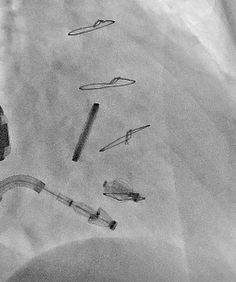

手术在经食道超声心动图和DSA引导下进行,武汉协和医院董念国教授团队使用NeoBlazar™经导管三尖瓣夹合器,经股静脉穿刺,送入导丝建立右心房通路,送入三尖瓣夹合器械,在右心房调整双层控弯导管,将第一枚夹合器置于三尖瓣前叶与隔叶间反流最大区域,在DSA与超声双重指引下跨瓣进行瓣叶的捕获与夹合,在经食道超声心动图反复确认手术效果后,释放三尖瓣瓣膜夹;第二枚夹合器顺利送至后隔交界,捕捉三尖瓣后叶和隔叶,确认瓣叶夹持稳固后释放夹合器。此次术中共植入2枚瓣膜夹,瓣膜夹位置和功能良好,术后即刻超声心动图评估三尖瓣反流降至轻度,手术取得圆满成功。

术中DSA图